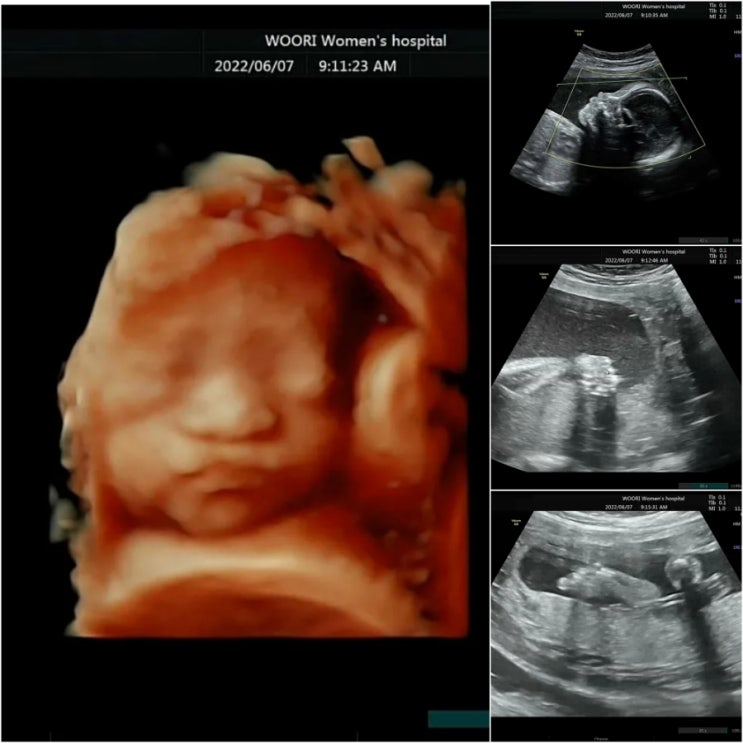

[임신20주&24주5일]임당검사